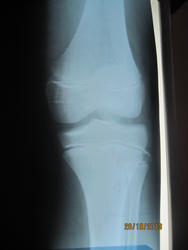

Кстати а 2и 3 снимок, где лево и право?

Подписала

Такое ощущение, что бугристость болшеберцовой кости фрагментирована справа.

Не похоже, чтобы тянул левый коленный сустав на артрит.

А на Осгуд-Шлаттера не тянет слева?